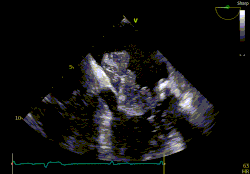

A betegreferálásra jelenleg heti két alkalommal van lehetőség, hétfőn és csütörtökön. A megbeszélések során a beteg anamnézisét és aktuális klinikai állapotát figyelembe véve, a rendelkezésre álló képalkotó vizsgálatok áttekintését követően születik multidiszciplináris döntés.

Az infekciózus endocarditis továbbra is komoly kihívást jelent a modern orvostudomány számára, magas morbiditási és mortalitási mutatóival még optimális kezelés esetén is.

A Heart Team rendszer mintájára 2023 januárjától elindítottuk az Endocarditis Team heti rendszerességgel működő multidiszciplináris referálási fórumát, amelyre minden szerdán van lehetőség.